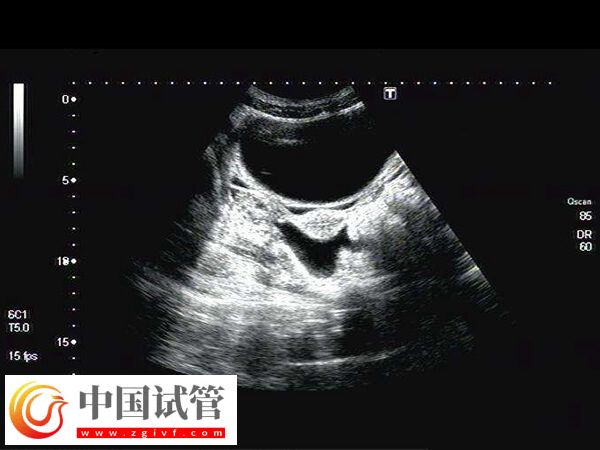

子宫动脉阻力高通常是指子宫动脉的血流受阻,这时子宫的血液供应不足,可能会引起局部缺氧和营养供应较差,如果此时进行移植,可能易发生胚胎停育、发育迟缓等情况,因此为改善此情况,患者在移植前可注射肝素,至于具体打多久时间,如下所示。